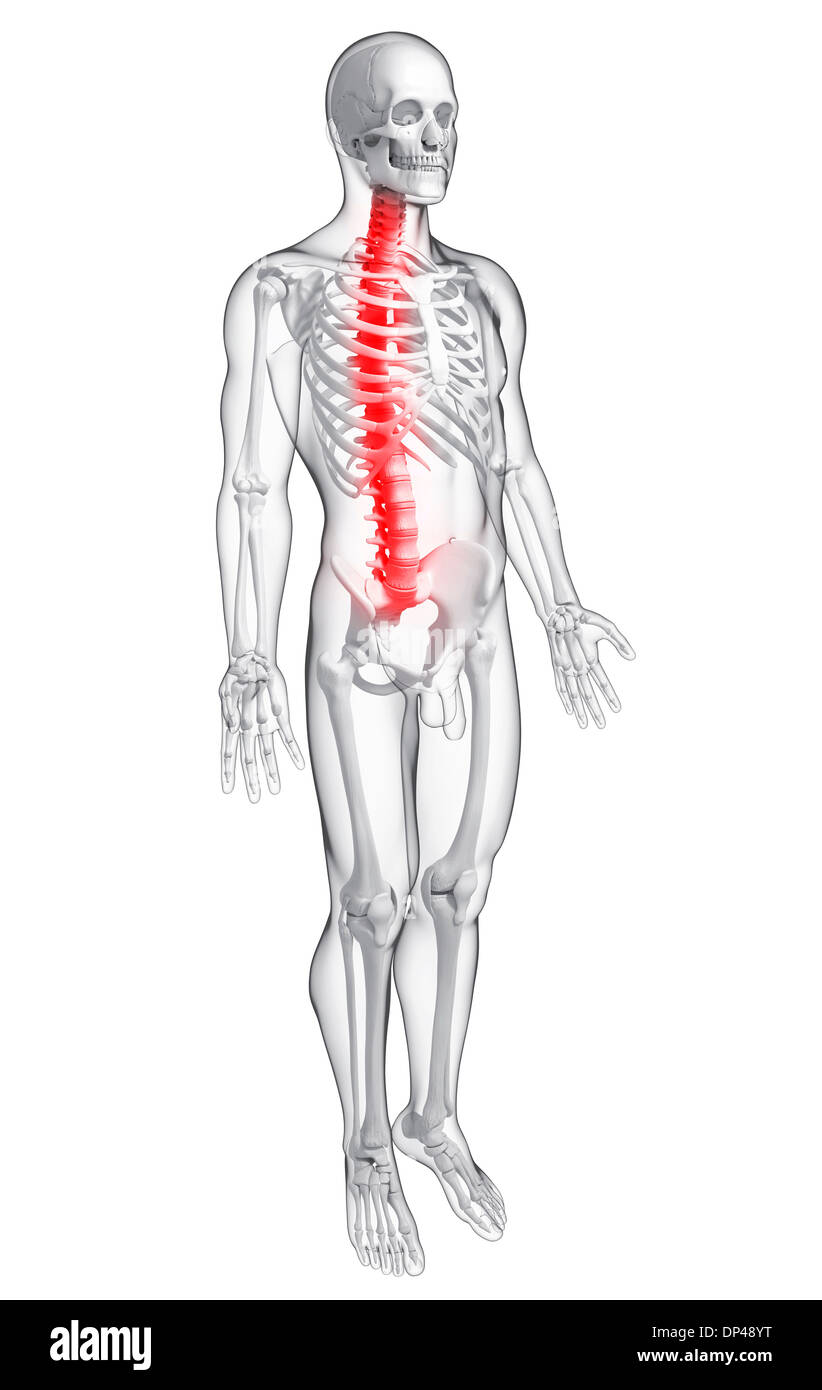

Back pain, artwork Banque D'Imageshttps://www.alamyimages.fr/image-license-details/?v=1https://www.alamyimages.fr/back-pain-artwork-image65248396.html

Back pain, artwork Banque D'Imageshttps://www.alamyimages.fr/image-license-details/?v=1https://www.alamyimages.fr/back-pain-artwork-image65248396.htmlRFDP48YT–Back pain, artwork